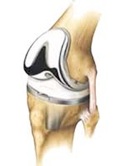

The operation involves a straight incision over the knee cap and replacing the cartilage of the knee with metal cap over the femur and tibia. These metal knee components are usually cemented in place and have a plastic liner/ insert in between. Sometime the knee cap also has a plastic cap cemented over it’s joint surface.

The majority of surgeons in the UK do not resurface the patella (knee cap). Instead they interrupt the nerve supply to it preserving the bone and relieving the pain. In a small number of cases patients can still have some discomfort from the knee cap and a resurfacing can be performed at a later stage. The reason for this reluctance to resurface the knee cap is the risk of potential complications including patella fracture and loosening of the component. Patients who suffer from Rheumatoid arthritis usually need to have their patellae resurfaced because the incidence of symptoms is higher.